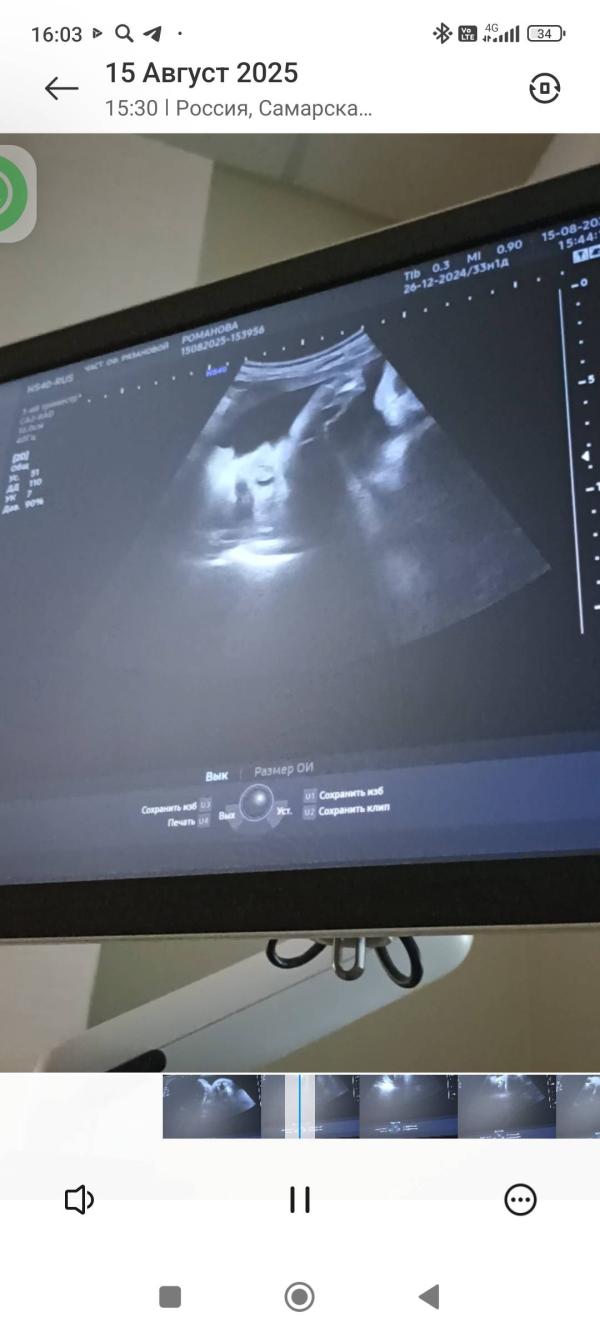

3-ий скрининг: все хорошо, малыш весит 2,166 кг!

Прошла 3-ий скрининг, все хорошо 🙏

На фото носик и сладкие пяточки 🥰 Весь уже не умещается на экране! 2,166 кг счастья!

Срок 33,1

15.08.2025